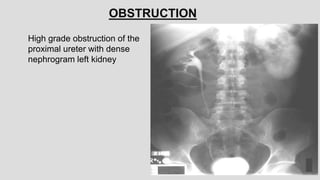

OBSTRUCTION

High grade obstruction of the

proximal ureter with dense

nephrogram left kidney